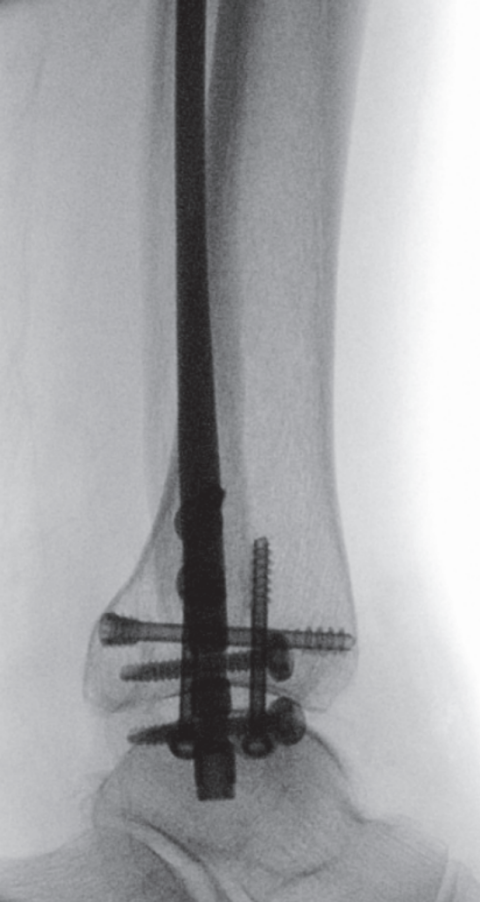

手术技术始于自腓骨尖向远端作短切口。锐性分离皮下组织,置入保护套筒。经套筒将导针置入髓腔并进入近端骨块。用空心开口器开髓,随后依次使用6.1毫米(远端)及3.1毫米、3.6毫米(近端)的钻头进行髓腔扩髓。扩髓过程在透视监控下进行,以避免皮质穿孔并确保钉道居中。将安装于瞄准器的腓骨髓内钉在透视引导下插入至预定深度,向外侧旋转,并用两枚前后向螺钉及两枚三皮质下胫腓联合螺钉锁定。未使用尾帽。最后于多平面进行透视记录(图5a–c)。彻底冲洗并止血后,将胫骨后肌腱复位,修复支持带,采用间断Donati缝合法分层闭合切口。敷以无菌敷料并用背侧夹板固定。

image.png

(a)

(b)

(c)

图 5. (a–c):最终术中透视图像:(a) 前后位视图,(b) 侧位视图,(c) 踝穴位视图。